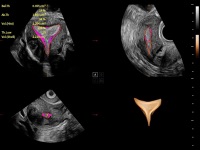

丰富的血流动力学检测技术,可在不同医疗场景中高效捕捉血流信号,助力临床诊疗。

在传统血流的基础上优化扫查和算法策略,能够更好的抑制组织信息,提炼红细胞运动信息,得到更高帧频,高灵敏度和分辨率的血流信号,还原更真实的血流动力学。

通过光照模型,使二维血流显示出立体的效果,增加血流的敏感性、成束性,减少外溢。可以和其他不同的血流技术联合使用,融合不同技术的优势。轻松应对微小血管,增强血流的立体效果,提升视觉敏感性。

通过创新的Matrix E自适应滤波算法,能有效滤除软组织和噪声信号,最大限度保留超低速微细血流的信号;结合超长时间域算法,极大提升细微血流的敏感性和空间分辨率,更真实的反应组织、包块的血流灌注情况。